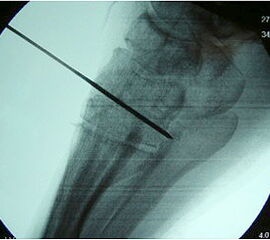

Radiologisches Beispiel einer fixierten Planovalgus Deformität Stadium III, 51 jähriger Patient. Stehendes präoperatives Röntgenbild und 1 Jahr postoperatives Röntgenbild des Fußes seitlich. Die Korrektur der Deformität umfaßte eine leicht korrigierende U

Abbildung 12

Im Stadium III der Tibialis posterior Sehneninsuffizienz bei fixierter Deformität und/oder erheblich eingeschränkter Inversion im USG aber stabilen und flexiblen Chopart-Gelenk und weniger als 10° fixierter Vorfußsupination eine in-situ oder leicht korrigierende USG-Arthrodese indiziert. Der Vorteil einer isolierten USG-Arthrodese gegenüber einer Triple- oder Double-Arthrodese ist die verbleibende, funktionell wichtige Beweglichkeit in der Chopart-Gelenkreihe. Um einem persistierenden fibulocalcanearem Impingement sicher vorzubeugen, sollte die USG-Arthrodese in maximal 5° Valgus- oder sogar Neutralposition erfolgen. Zur Prophylaxe eines Rezidivs wird die USG-Arthrodese zudem häufig mit einer medialisierende Tuber calcanei Osteotomie und / oder einem FDL-Transfer kombiniert (Abb. 12).